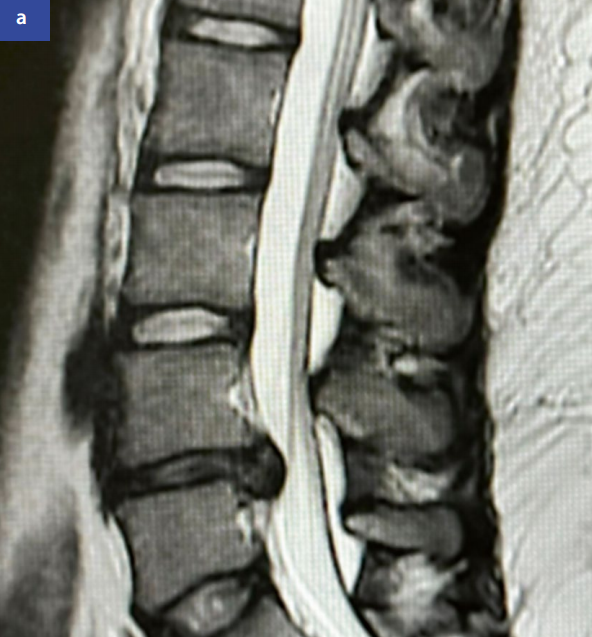

MRIMRI(图1)在软组织分辨率上优于CT,可清晰显示神经、关节和脊髓。诊断神经压迫的敏感性达93%。

图1:颈椎磁共振成像矢状位(a)和轴位(b)显示C5/C6节段右侧中外侧椎间盘突出(红色箭头标示)